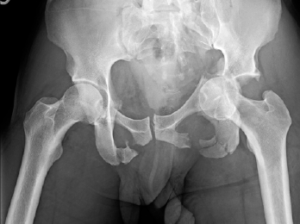

Lateral compression pelvic ring injury and left-sided T-shaped acetabulum fracture.